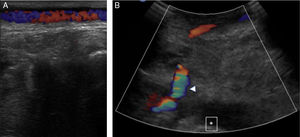

Figure 1.

Lateral X-ray of the knee: exophytic bone lesion (arrow) tibia-dependent corresponding to an epiphyseal osteochondroma.

A male, 67 years of age, obese, with high blood pressure and dyslipidemia presented at the emergency department due to pain, cold and functional impairment of his lower left limb of 24-h onset. During anamnesis, the patient stated he had had a chronic intermittent pain in his left knee for a long time. A previous simple knee X-ray showed an osteochondroma (Fig. 1). The patient presented with a femoral pulse but with no popliteal and distal pulses. Artery examination was normal in the contralateral extremity. A CT angiogram was requested for the lower limbs which showed thrombosis of the popliteal artery adjacent to the osteochondroma (Figs. 2 and 3). We decided to perform in situ revascularization with femoro-popliteal saphenous vein graft (Fig. 4) avoiding the tunneling technique for anatomical positioning. To date, after 3 years of follow-up with eco-Doppler, the bypass continues maintaining permeability with ankle-arm index of 0.9, and no signs of popliteal vein injury.

Osteochondroma is the most common pseudotumoral bone lesion. The radiologic pathognomonic characteristic of this tumor is the cortical and medullar continuity of the lesions with the bone from which they protrude.1 They may be single or multiple.2 Some of the most common complications are the presence of bone deformity, fractures,1 vascular compromise3 and neurological compromise,4 formation of a bursa5 and malignant degeneration.6 Diagnosis may be made with an X-ray, although other imaging methods such as a scan, CT and MR may be used in suspected cases when symptoms occur or are in unusual locations.1 Vascular compromise may be caused by displacement of blood vessels (arteries and veins), by stenosis, occlusion and the formation of pseudoaneurisms, with the latter being more frequent at knee level,7 involving the popliteal artery or being presented as arterial thrombosis,8,9 as in this clinical case. Its presentation as thoracic outlet syndrome in the case of rib lesions has been described.10